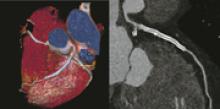

Physicians have used radiation in medicine for more than a century. The use of radiation in diagnostic imaging, including computed tomography (CT), fluoroscopy, angiography, mammography, computed radiography (CR) and digital radiography (DR), as well as in nuclear medicine, has aided greatly in the diagnosis and treatment of cancer and other diseases.